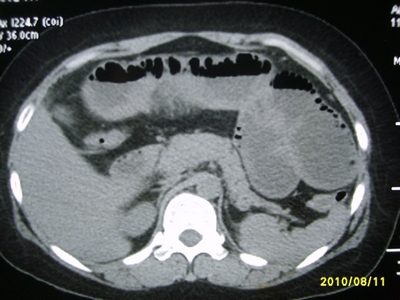

5天前突发腹痛剧烈难忍,伴解淡血水样便。近一天来腹痛缓解,没有明显的腹膜炎的体征。今天照的腹部ct。从ct上看感觉是一个绞窄性肠梗阻,但是现在没有腹痛。不好解释

请放射科的专家,帮帮看看。从影像学的角度来看看。这是不是一个绞窄性肠梗阻。

要有麻烦了,感觉小肠有套叠还有扭转改变,估计部分已有坏死。

高位肠梗阻(不全性),原因小肠(空肠)扭转,肠壁水肿增厚,成年人肠梗阻要排除合并占位,建议手术。

绞窄性肠梗阻_肠管套叠 扭转,肠壁明显水肿。

病人现在没有腹痛。怪了。从影像上来看。确实是绞窄了。但是没有腹痛。没有明显的腹膜炎的体征。确实有不好解释。难道是坏死了。反而不痛了。怪怪怪

支持绞窄性肠梗阻,肠壁明显水肿并见有多发小泡状积气--肠坏死

考虑绞窄性肠梗阻并肠坏死。